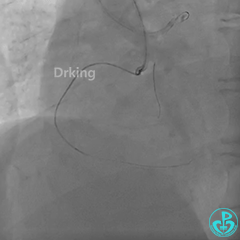

左冠造影:

导丝怎么扩收藏:器械难以通过的CTO病变之技术图谱_https://www.jmylbn.com_新闻资讯_第4张